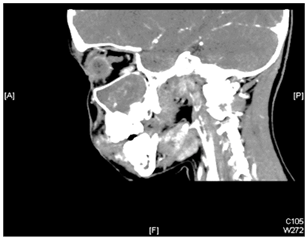

A 9 years old girl, presented with longstanding, left sided nasal obstruction and serosanguinous nasal discharge. She had been experiencing nasal obstruction and intermittent epistaxis for one year already. Her past medical history was otherwise unremarkable. The patient on anterior rhinoscopy, a bulge was detected, arising from the left nasal wall and impinging on the septum. The computed tomography (CT) examination was performed on a spiral scanner. The CT scan obtained following intravenous contrast administration revealed a large, inhomogeneously enhancing mass in the left maxillary sinus and nasal cavity (Figure 1–3). The nasal turbinates and the medial wall of the maxillary sinus had been eroded by the mass. There was also a bony remodeling in the anterior wall of the maxillary sinus. Because of the suspicion of sinonasal cancer, a biopsy was taken to obtain tissue from the nasal cavity and maxillary sinus. However, the biopsy revealed multiple submucosal dilated vessels filled with blood, fibrin deposition and organized thrombi stain for fungal organism negative, findings consistent with hemangioma. The microscopic examination showed dilated sinusoidal vascular channels in the stroma lining with an interconnecting fibrous wall covered with flat endothelium. The Lumina of these spaces were filled with blood. The histologic features were most compatible with cavernous hemangioma (Figure 4). On follow up, patient improvement regarding nasal obstruction and less nasal bleeding.

Figure 4 Multiple sub mucosal dilated vessels filled with blood, fibrin deposition and organized thrombi. Stain for fungal organism is negative. Findings consistent with Hemangioma “Cavernous Hemangioma”